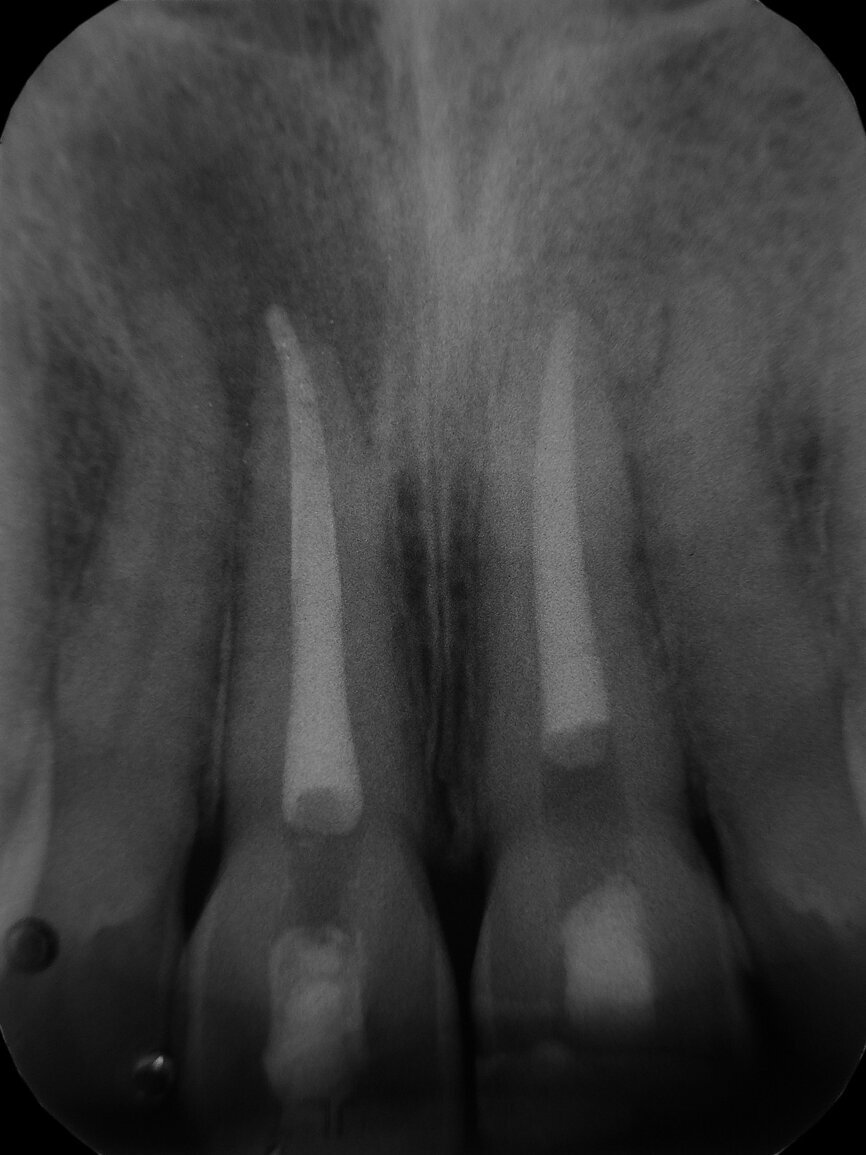

The 22-year-old male patient had a history of trauma to his maxillary incisors and arrived at my practice with symptoms related to tooth #21. The tooth, opened in an emergency by the patient’s mother, was tender when prodded, with a moderate level of sensitivity on the respective buccal gingiva. Sensitivity tests were negative for the other central incisor (tooth #12 was positive), and a periapical radiograph showed radiolucency in the periapical areas of both of the central incisors. The apices of these teeth were quite wide and the length of teeth appeared to exceed 25 mm.

After isolating with a rubber dam, I removed the temporary filling, and then the entire pulp chamber roof with a low-speed round drill. The working length was immediately evaluated using an electronic apex locator and a 31 mm K-type file. The working length was determined to be 28 mm.

As can be seen in the photographs, the canal was actually quite wide, so I decided to only use an irrigating solution and not a shaping instrument. Root canals are usually shaped so that there will be enough space for proper irrigation and a proper shape for obturation. This usually means giving these canals a tapered shape to ensure good control when obturating. With open apices, a conical shape is not needed, and often there is enough space for placing the irrigating solution deep and close to the apex.

I decided to use only some syringes containing 5 per cent sodium hypochlorite and EDDY, a sonic tip produced by VDW, for delivery of the cleaning solution and to promote turbulence in the endodontic space and shear stress on the canal walls in order to remove the necrotic tissue faster and more effectively. After a rinse with sodium hypochlorite, the sonic tip was moved to and from the working length of the canal for 30 seconds. This procedure was repeated until the sodium hypochlorite seemed to become ineffective, was clear and had no bubbles. I did not use EDTA, as no debris or smear layer was produced.

I suctioned the sodium hypochlorite, checked the working length with a paper point and then obturated the canal with a of 3 mm in thickness plug of bioactive cement. I then took a radiograph before obturating the rest of the canal with warm gutta-percha. I used a compomer as a temporary filling material.

The symptoms resolved, so I conducted the second treatment only after some months, when the tooth #11 became tender. Tooth #21 had healed. I performed the same procedure and obtained the same outcome (the four-month follow-up radiograph showed healing).